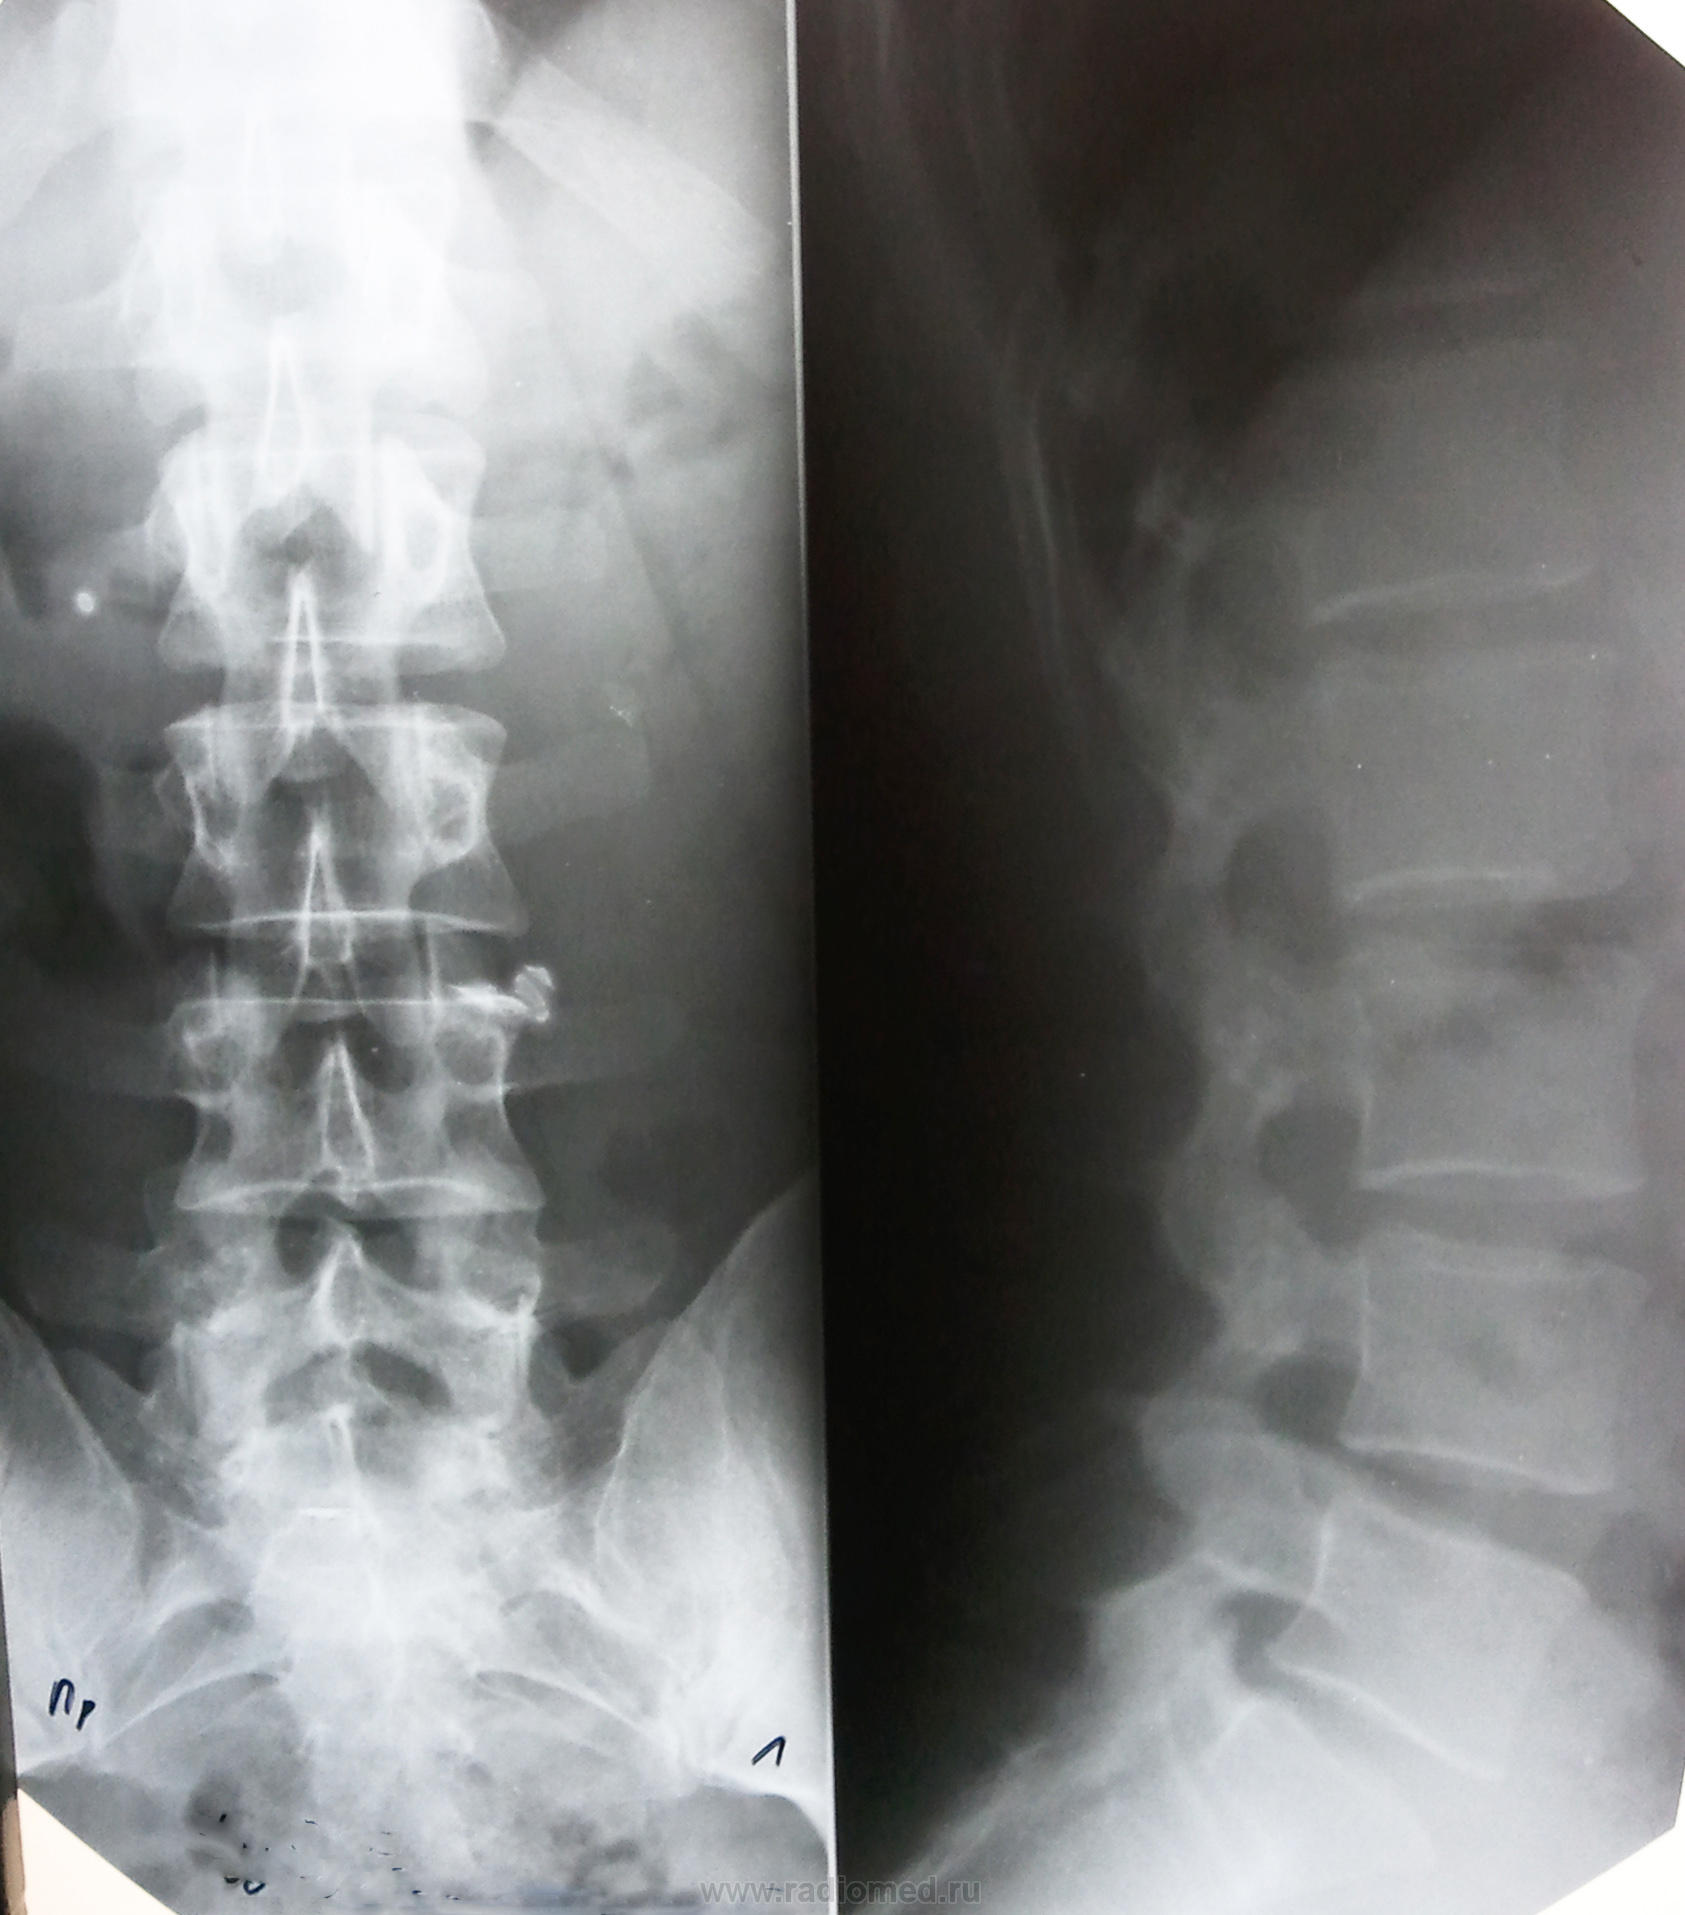

Костяк на вид довольно молодой: лет 35-40 можно дать. Хотя в сегменте Th12-L1 и остеохондроз, и спондилоартроз имеются. Предполагаю: окажется вдвое больше).

ответ: это позвоночник мужчины кавказской национальности, 72 лет. Когда увидел снимок, расспросил лаборантов о пациенте, сказали выглядел хорошо, моложе своих лет. Вот как бывает..

Можно утверждать, что больше 20-ти. Все апофизы и точки окостенения сраслись. Верхний предел назвать не берусь. Здесь как кому повезёт.

Горный воздух, простая пища, незамаранная совесть, незамутнённая наследственность очень способствуют…